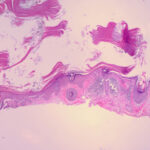

The bowenoid type of actinic keratosis is histologically indistinguishable from Bowen’s disease and may also be referred to as squamous cell carcinoma in situ. As in Bowen’s disease, within the epidermis there is considerable disorder in the arrangement of the nuclei, as well as clumping of nuclei and dyskeratosis